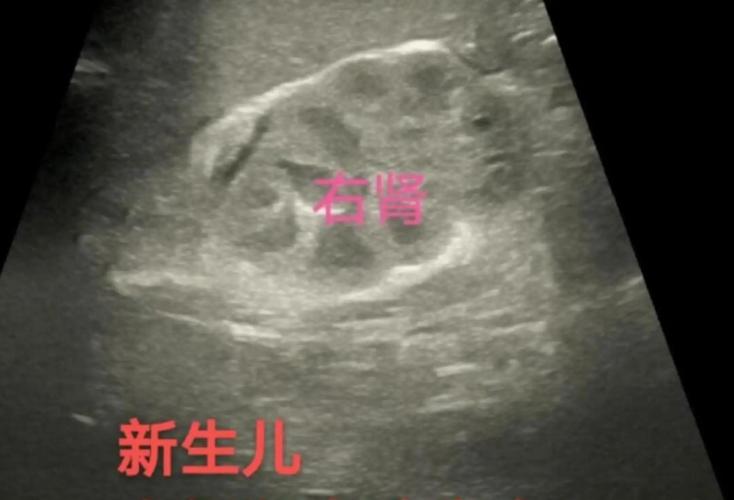

新生儿肾上腺皮质增生症,简称CAH,是一组由于肾上腺皮质激素合成过程中所需酶的缺陷所引起的遗传性疾病,这个缺陷导致身体无法正常合成皮质醇和/或醛固酮,而一些中间产物(如雄激素)则会异常增多。

根据缺乏酶的种类和严重程度,CAH可以分为多种类型,其中21-羟化酶缺乏症最为常见(约占95%),其症状也最具代表性,我们主要以此为例来介绍症状。